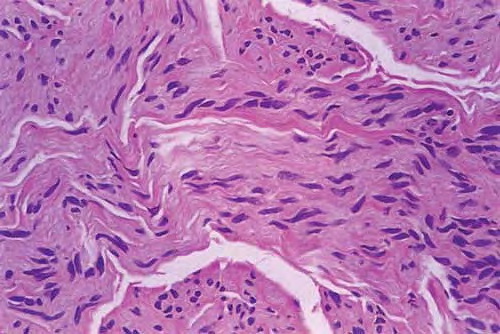

Palisaded encapsulated neuroma = الورم العصبي المحاط بمحفظة وسياج